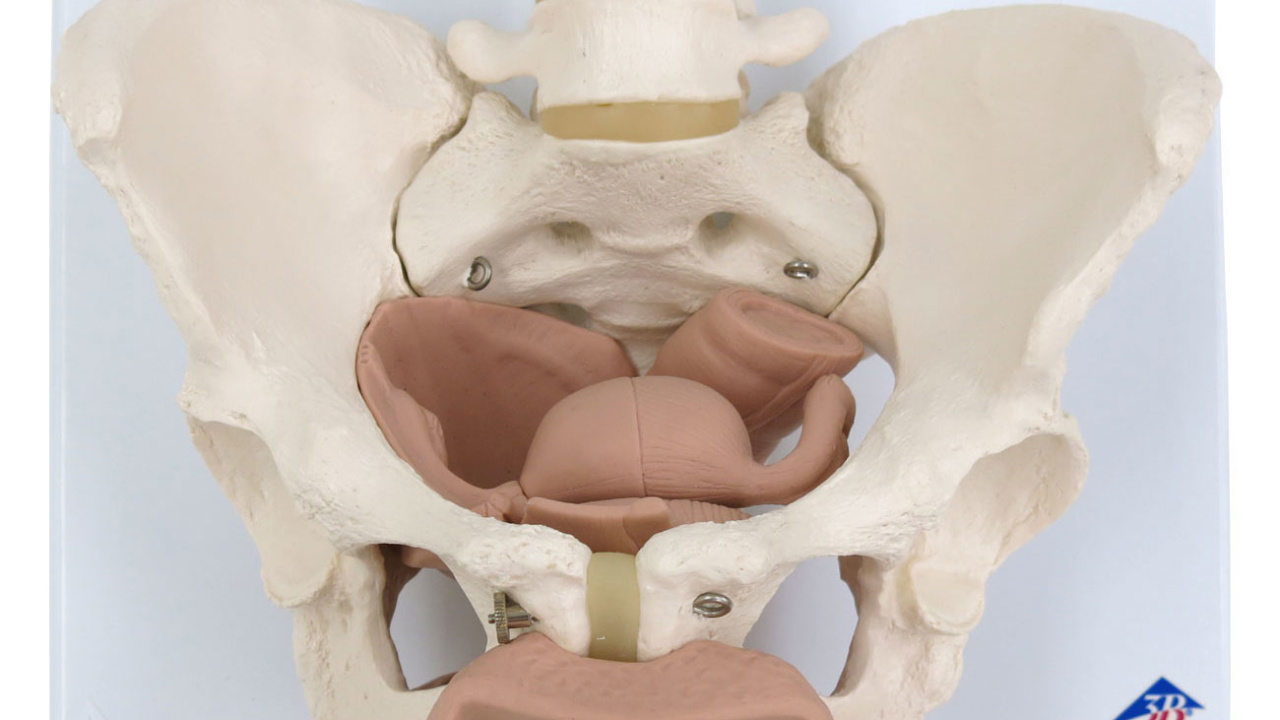

沸騰ブラドン 女性骨盤モデル(可動型) 日本スリービー 25-3004-00 人体模型 人体模型の詳細情報

女性骨盤モデル(可動型) 人体模型 25-3004-00 日本スリービー。8000837-900x900.jpg。Amazon.co.jp: 実物大の女性骨盤模型 - 女性骨盤モデル,大腿骨。BEURRE 焼酎 3本セット。解剖学的教育に最適な骨盤模型、NFC機能付き。女性骨盤モデル,大腿骨付 | 日本スリービー・サイエンティフィック。女性日本スリービー・サイエンティフィック株式会社定価1.8万ほどで購入- モデル: 骨盤模型- 特徴: NFC機能付き- 用途: 解剖学的教育用- 材質: プラスチック- サイズ: 約30cm x 20cmご覧いただきありがとうございます。タケヤ式自在置物 骸骨 鉄錆地調 KT Project KT-005。